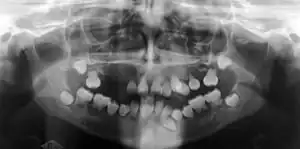

Preoperative panoramic radiographs showing features of dentin dysplasia type I | |

Radiographic feature

In other words, affected primary teeth usually have abnormal shaped or shorter than normal roots. “Crescent/half-moon shaped” pulp chamber remnant in permanent teeth can be seen on x-rays. The roots may appear to be darker or radiolucent/pointy and short with apical constriction. Dentine is laid down abnormally and causes excessive growth within the pulp chamber. This will reduce the pulp space and eventually cause incomplete and total pulp chamber obliteration in permanent teeth.[12][13] Sometimes periapical pathology or cysts can be seen around the root apex.[11] Most cases of DD associated with peri-apical radiolucency/ pathology have been diagnosed as radicular cysts, but some of them have been as diagnosed peri-apical grauloma instead.[14]